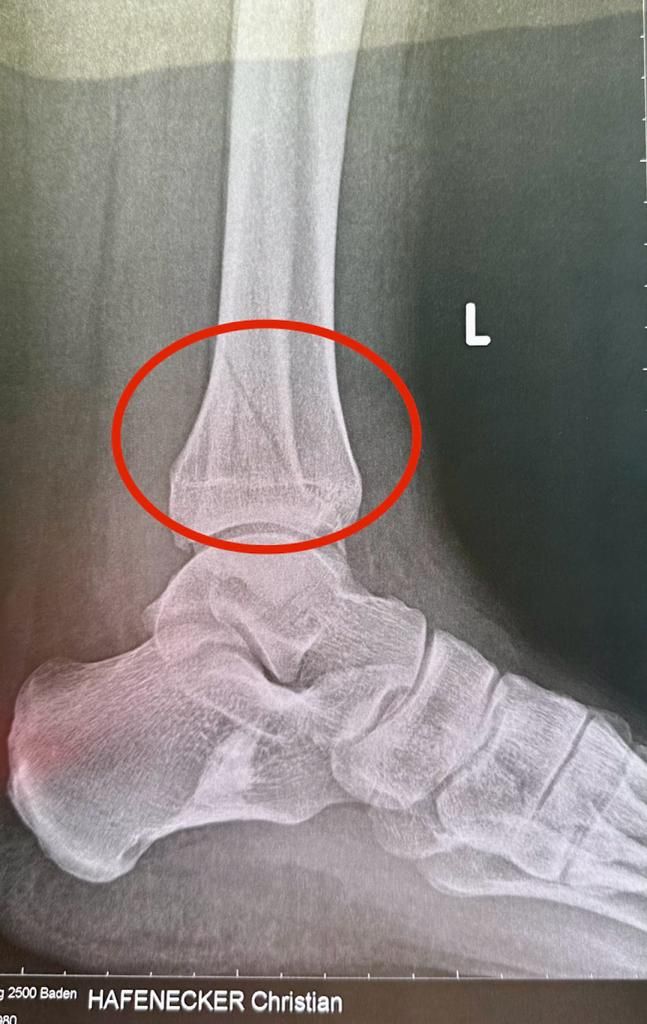

FPÖ-Generalsekretär Christian Hafenecker hat sich das Bein gebrochen! Das hat der 42-Jährige selbst auf seinem Twitter-Account mitgeteilt.

Laut "Heute"-Infos ist der FPÖ-Mann bereits am Dienstag auf Glatteis gestürzt. Nach dem Unfall habe er dann geglaubt, "es wird schon wieder!" Doch am Freitag dann die Schock-Nachricht: Spiralfraktur des linken Wadenbeins. Hafenecker wurde daraufhin operiert und bleibt über das Wochenende im Spital.

Christian Hafenecker hat sich das Bein gebrochen – am 13. Februar wird er aus dem Spital entlassen.